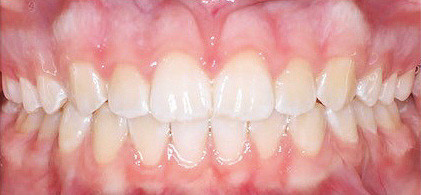

Klinisches Fallbeispiel 2 (Abb. 2a–y)

Distalbiss und tiefer Biss bei einem zwölfjährigen Mädchen. Die Behandlung erfolgte mit Invisalign und Precision Wings. Insgesamt waren zwei Schienensätze notwendig. Die Gesamtbehandlung dauerte 18 Monate.Bei der Planung des ClinCheck wurde der tiefe Biss vorwiegend über eine Intrusion der Unterkieferfront behoben, um die Lachlinie der Patientin nicht negativ zu beeinflussen. Die Oberkieferfront wurde nur retrudiert, jedoch vertikal nicht intrudiert. Während der Phase des Mandibular Advancement wurde die Wirkung der Precision Wings durch den Einsatz von Klasse II-Gummizügen unterstützt. Schlussendlich wurde auch der hängenden Okklusionsebene durch eine einseitige Intrusion der Molaren im ersten Quadranten Rechnung getragen.